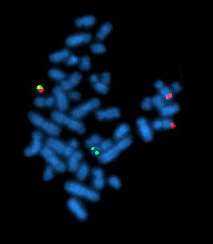

Fluorescence in situ hybridization (FISH) is a cytogenetic technique that uses fluorescent probes that bind to only those parts of the chromosome with a high degree of sequence complementarity. It was developed by biomedical researchers in the early 1980s[1] and is used to detect and localize the presence or absence of specific DNA sequences on chromosomes. Fluorescence microscopy can be used to find out where the fluorescent probe is bound to the chromosomes. FISH is often used for finding specific features in DNA for use in genetic counseling, medicine, and species identification.[2] FISH can also be used to detect and localize specific RNA targets (mRNA, lncRNA and miRNA) in cells, circulating tumor cells, and tissue samples. In this context, it can help define the spatial-temporal patterns of gene expression within cells and tissues.

The mixture of probe sequences determines the type of feature the probe can detect. Probes that hybridize along an entire chromosome are used to count the number of a certain chromosome, show translocations, or identify extra-chromosomal fragments of chromatin. This is often called "whole-chromosome painting." If every possible probe is used, every chromosome, (the whole genome) would be marked fluorescently, which would not be particularly useful for determining features of individual sequences. However, it is possible to create a mixture of smaller probes that are specific to a particular region (locus) of DNA; these mixtures are used to detect deletion mutations. When combined with a specific color, a locus-specific probe mixture is used to detect very specific translocations. Special locus-specific probe mixtures are often used to count chromosomes, by binding to the centromeric regions of chromosomes, which are distinctive enough to identify each chromosome (with the exception of Chromosome 13, 14, 21, 22.)

A variety of other techniques use mixtures of differently colored probes. A range of colors in mixtures of fluorescent dyes can be detected, so each human chromosome can be identified by a characteristic color using whole-chromosome probe mixtures and a variety of ratios of colors. Although there are more chromosomes than easily distinguishable fluorescent dye colors, ratios of probe mixtures can be used to create secondary colors. Similar to comparative genomic hybridization, the probe mixture for the secondary colors is created by mixing the correct ratio of two sets of differently colored probes for the same chromosome. This technique is sometimes called M-FISH.